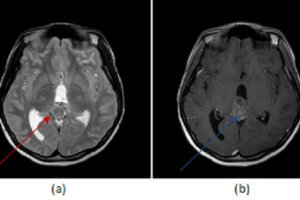

Tectal Plate Glioma

Masses of the pineal region can be divided into pineal and non pineal. Non pineal masses can arise from any of the structures in the region and include glioma (from the tectum... Read more »

Pineoblastoma

Tumors of the pineal gland can be categorized into pineal cell and germ cell depending of their cell type of origin. Unlike germ cell tumors, pineal cell tumors tend to expand the... Read more »